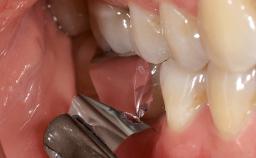

Open-Flap Debridement for the Management of Peri-Implant Mucositis Associated with Excess Cement

A 79-year-old female patient was referred to the Department of Periodontology of the University of Bern, Switzerland by her private dentist in May 2019. She had been rehabilitated in May 2005 with two tissue-level implants (Institut Straumann AG, Basel Switzerland) at sites 13 and 15, supporting a three-unit cemented fixed dental prosthesis (FDP). The metal-ceramic FDP had been cemented permanently with a glass-ionomer cement (Ketac Cem; 3M ESPE, Seefeld, Germany). Implant 13 had been diagnosed with peri-implant mucositis by the referring dentist in the course of regular supportive therapy. The patient was in good general health, did not smoke, and exhibited good self-performed plaque control.